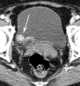

Bladder cancer

Bladder cancer is any of several types of cancer arising from the tissues of the urinary bladder. Symptoms include blood in the urine, pain with urination, and low back pain.Risk factors for bladder cancer include smoking, family history, prior radiation therapy, frequent bladder infections, and exposure to certain chemicals. [Source: Wikipedia ]